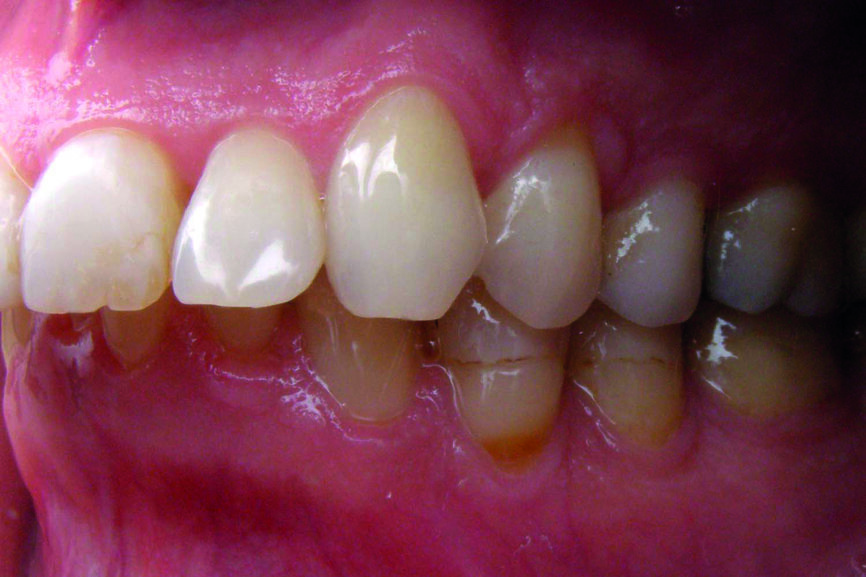

D’un point de vue dentaire le patient présente une Classe II division 1, avec une classe II molaire complète et une classe II canine.

- Présence d’un overjet et d’une supraclusion résiduelle.

- L’arcade supérieure est régulière mais les incisives sont en vestibulo version importante.

- L’arcade inférieure présente un encombrement dans le secteur antérieur associé à une version vestibulaire.

- Les milieux correspondent.